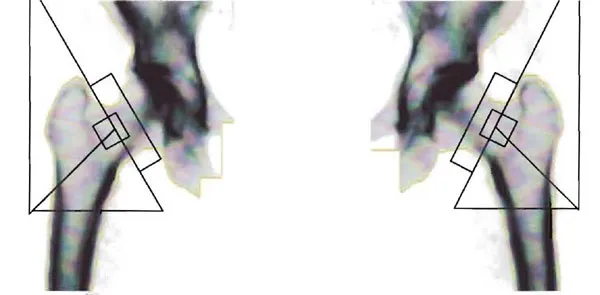

Section titled “DEXA Part Two: The Hip Scan”Last month I wrote about my patient, Mary, who came to me with a DEXA scan that indicated she was at risk for fractures and recommended she take medication to prevent them. It bothered me that her report was unjustifiably alarming. Last month we examined the scan of her spine. Now let's look at the scan of her hip, which was accompanied by a report that was also falsely alarming. Here is the actual image captured by the scanner.

Figure 1

The degree of darkness of the bones was used by the scanner to estimate the bone "density." (See last month's newsletter about the fallacy of calling this shadow "density." Here is how Mary's results are plotted on a graph.